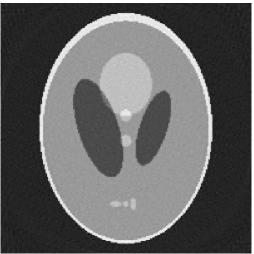

Furthermore, we used the classic ART iteration as the iteration operator in our numerical experiments. In order to compare the proposed superiorization algorithm with the classic superiorization algorithm, we applied the classic superiorization and -PP superiorization algorithm to two phantoms (see figure 1). The first one is the Shepp-Logan phantom[30], and the second one is the head phantom with a ghost which is invisible at 22 specified projection directions [10, 31]. In addition, we compare the performances of the two algorithms for the noiseless and noised data with different projections. In all experiments, the noised projection data was corrupted by additive Gaussian white noise with variance . We record the iterations, running time of program and mean square error (MSE) of different algorithms, where MSE is computed by

The reconstruction images from the noiseless projection data were shown in the Fig. 2. From Fig. 2, we can observe that the classic and the proposed algorithms can reconstruct images from the three projection data. In order to show the advantages of the proposed algorithm visually, the central vertical line of the differences between the reconstructed images and the original image are present in Fig. 3. We can observe that the -PP superiorization is more efficient than the classic superiorization in the aspect of suppressing the artifacts in the reconstructed images.

In order to compare the images in Fig. 2 quantitatively, we tabulated the iterations, MSE, Res and running time(RT) of programs in Table 1. By comparing the numbers in Table 1, we can draw the conclusion that the proposed method can improve the quality of the estimated images and save computation time.

3.2 Ghost phantom

Noiseless projection data: Since the ghost in this phantom is invisible at 22 directions [10, 11], the reconstruction images usually suffer from artifacts. in our simulations, the projection data were collected in 112 and 82 directions: 90 and 60 with equal angle increments from to and 22 specified views in which the ghost is invisible [10]. Iteration procedures were terminated when for the noiseless projections.

The reconstruction images from the noiseless projection data were shown in the Fig. 6. For comparison, Table 3 present the iterations, MSE, Res and running time(RT) of different reconstruction results.